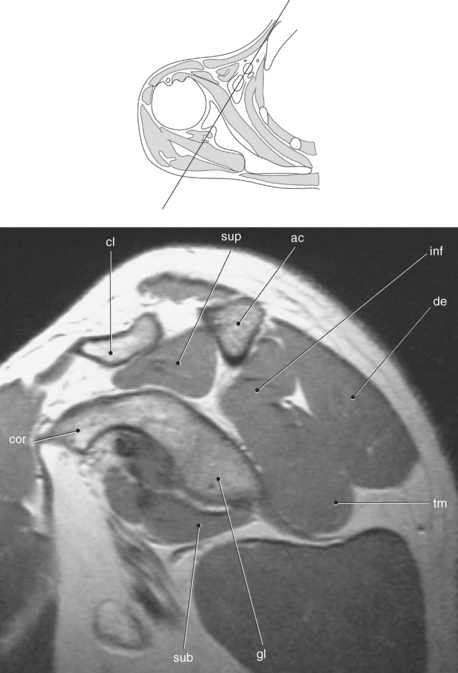

Figure 9.10 Sagittal oblique, T1-weighted MR scan of shoulder.

Key: cor, Coracoid process; cl, clavicle; sup, supraspinatus; ac, acromion; inf, infraspinatus; de, deltoid; tm, teres minor; gl, glenoid; sub, subscapularis; h, humerus; grt, greater tubercle; sc, scapula; glf, glenoid fossa; hh, humeral head.